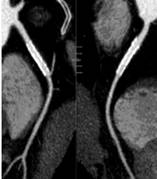

标准规定的临床影像技术检查项目,在脑血管疾病、心血管疾病、系统肿瘤、五官科疾病诊断方面形成特色。科室目前拥有西门子炫速双源螺旋CT,东芝320排螺旋CT及西门子64层螺旋CT,其中东芝320排螺旋CT、西门子双源CT均拥有更快的扫描速度,更高的图像质量和分辨率,更强大的后处理工作站,更广泛的临床应用领域,更低的放射剂量,在呼吸、骨骼、胃肠、神经、心血管等专科领域应用广泛。科室承担多项省部级科研基金资助项目,常年承担西安交大法医系、延安大学影像专业、西安医学院学生及基层医生实习和进修的带教任务,与省内部分地区开展了远程会诊业务,赢得了较高的社会声誉。

320排螺旋CT具备16cm宽覆盖探测器,实现动态容积扫描,360度的各向同性采集能力及[email protected]%密度分辨率的量子探测器,一次心跳全心脏采集,一圈扫描器官成像,一次检查完成多重任务,实现真正的动态容积体灌注及心脏、神经一站式检查;西门子Flash炫速CT扫描系统,具备两套同时旋转的X射线球管及探测器,实现了43cm/s的极快CT扫描速度和75 ms的时间分辨率,完成全胸扫描仅需0.6秒,使得患者做心脏扫描时无须食用β-受体阻滞药,亦无须屏气,并可实现低于1mSv的超低辐射剂量,配置第二代双能量、宽151级纯化能谱,组织鉴别能力进一步提高,可开展多达10余种双能量成像应用。